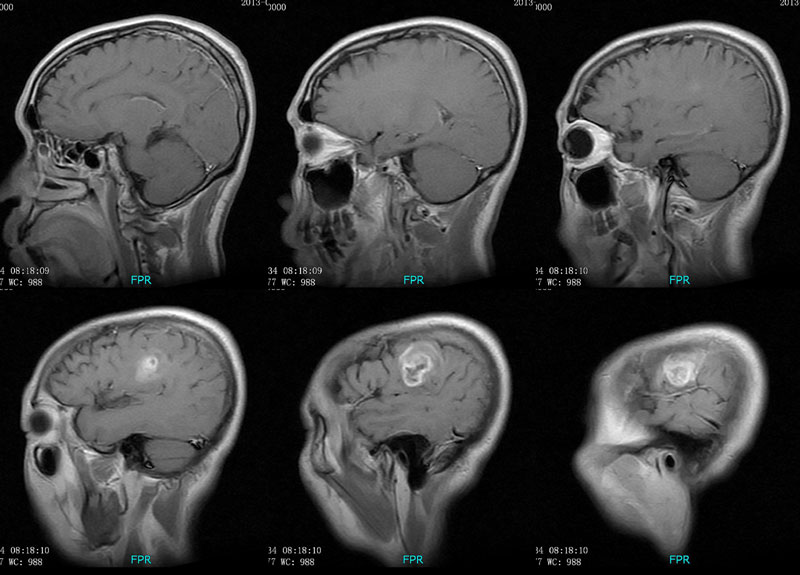

男性,46岁。

主诉:头晕、头痛2月余,加重10天。

现病史:患者2月余前出现头晕,呈天旋地转,阵发性,伴头痛,多于下午发作,伴右侧口角麻木。近10天患者自觉头晕头痛症状加重。

术后病理多形性胶质母细胞瘤 WHO Ⅳ级。

免疫组化:Vimentin(+),GFAP (+),MGMT个别(+),P53约10%(+),Ki67约20%。

胶质母细胞瘤,并侵犯硬脑膜。

CT平扫呈环形稍高密度,MRI呈长T1长T2,信号稍欠均匀,增强扫呈不规则环形强化,邻近脑膜增厚并明显强化。

左侧顶叶斑片状异常信号,T1低信号,T2高信号,增强后不均匀强化。左侧顶叶多形性胶质母细胞瘤,学习了。